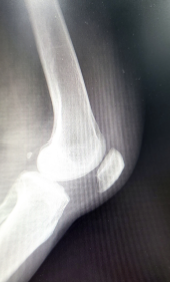

글루코사민 효능 부작용 적정섭취량 및 글루코사민에 대해 알아보도록 하겠습니다. 글루코사민은 우리 몸의 연골, 인대, 힘줄 등을 구성하는 중요한 성분입니다. 연령이나 운동, 관절염 등의 영향으로 글루코사민의 합성이 감소하면 관절의 퇴행이나 염증이 발생할 수 있습니다. 그래서 글루코사민을 보충하는 것이 관절 건강에 도움이 됩니다.

1. 관절 통증 완화: 글루코사민은 연골 조직 형성에 필수적인 성분이며, 연골 재생을 촉진할 수 있습니다. 연골이 손상되면 관절염이 발생하고 통증이 생기는데, 글루코사민은 이를 예방하거나 완화할 수 있습니다.

2. 항염증 작용: 글루코사민은 강력한 천연 항염증 물질로, 관절염이나 스포츠 부상 등으로 인한 염증을 줄여줍니다. 염증은 통증과 불편감을 야기하고, 관절의 기능을 저하시키는 원인이 됩니다.